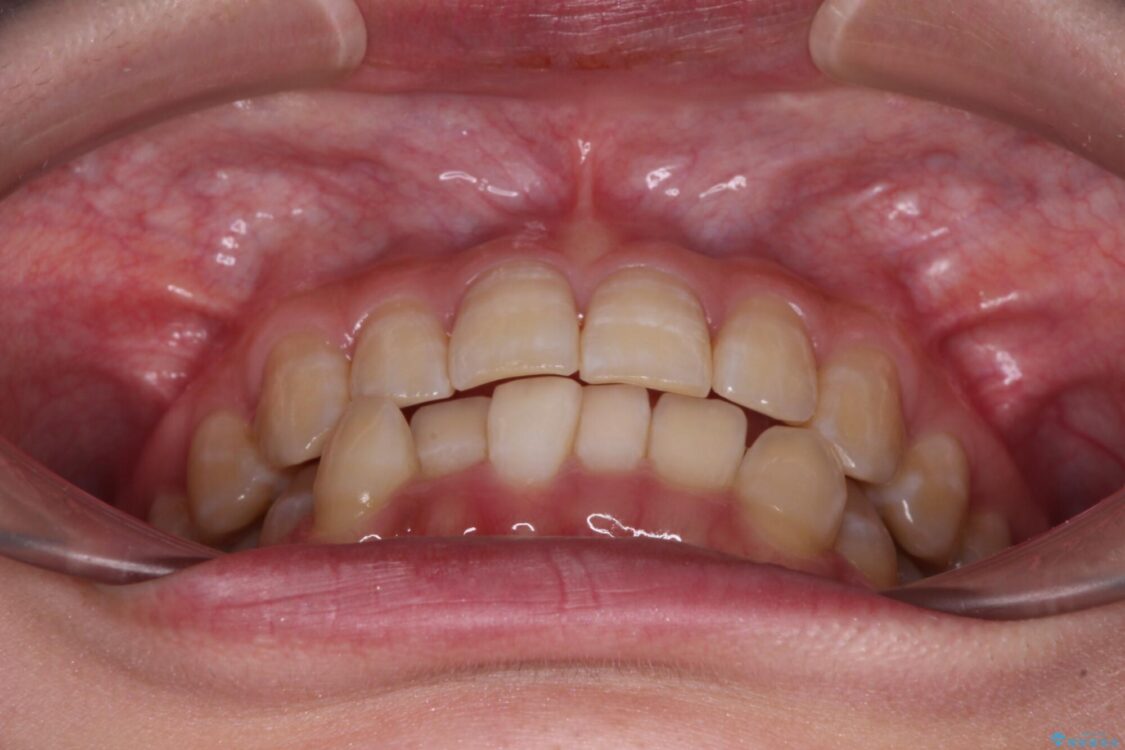

治療前、下顎前歯のデコボコが集中しており、奥歯の咬み合わせは、上顎に対して下顎が前方位にある状態でした。下顎の歯列を後方へ移動させる治療はインビザラインの得意とするところですので、1年程度で無事に治療を終えることができました。

治療後

• 【モニター】下顎前歯のデコボコをインビザラインできれいに 治療後画像